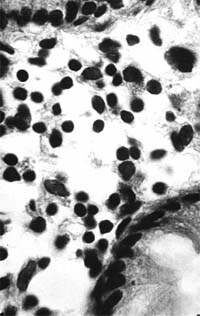

| Рисунок 2. Слизистая оболочка толстой кишки при ротавирусном гастроэнтерите. Минимальное содержание плазматических клеток в собственной пластинке, увеличение в ней числа макрофагов. х 400 |

В клинической практике врач нередко сталкивается с обстоятельствами (сомнительные результаты вирусологических и серологических исследований, случаи микст-инфекций), когда возникает необходимость в применении дополнительных методов для верификации диагноза. С этой целью может быть использован доступный для практического здравоохранения интрументальный метод исследования — ректороманоскопия с аспирационной биопсией слизистой оболочки толстой кишки. При гистологическом, морфометрическом и гистохимическом исследованиях биоптатов при ротавирусном гастроэнтерите выявляются характерные изменения в виде поверхностного минимально выраженного катарального колита с незначительной дистрофией эпителия (рис. 1), снижения числа серотонинсодержащих желудочно-кишечных эндокриноцитов (ЕС-клетки) в эпителиальном пласте кишечных желез, умеренной инфильтрацией собственной пластинки плазматическими клетками и увеличением в ней числа макрофагов (рис. 2). Эти особенности имеют дифференциально-диагностическое значение, поскольку отличаются указанным показателем от других острых кишечных инфекций, что может быть использовано в диагностически сложных случаях.